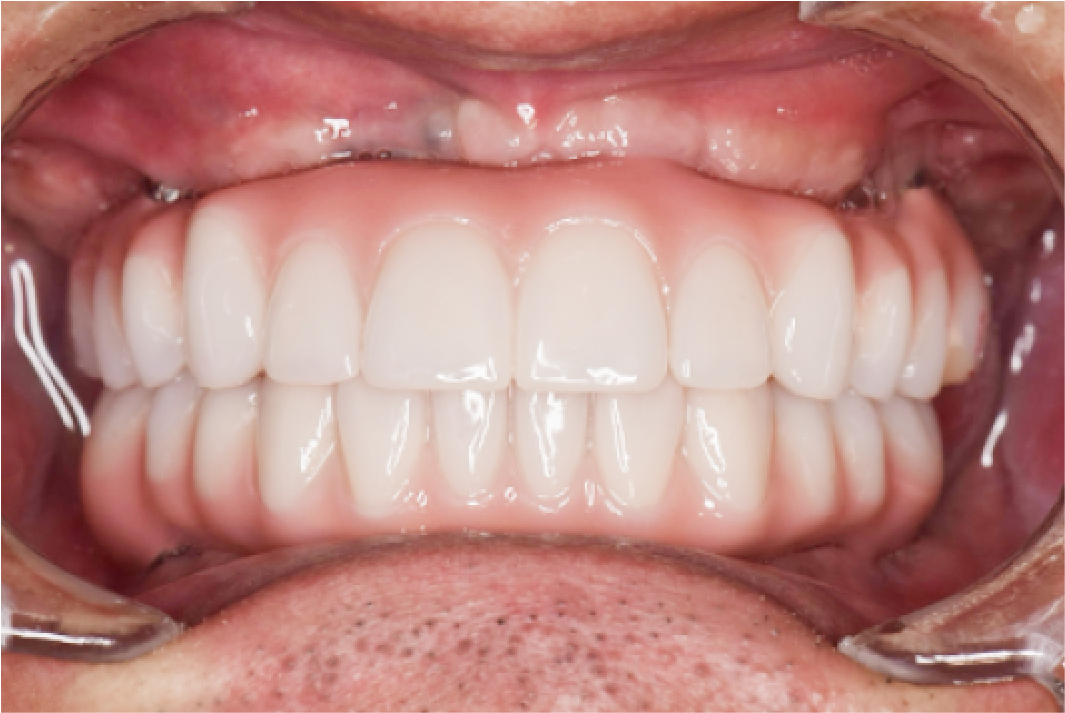

CASE04

■ 治療内容

上下顎All-on-4インプラント治療

■ 治療費用

6,627,000円(税込)

■ 治療期間

約9ヶ月

■ リスク

治療後の腫れや出血、またメンテナンスを怠ることで周囲炎のリスクあります。